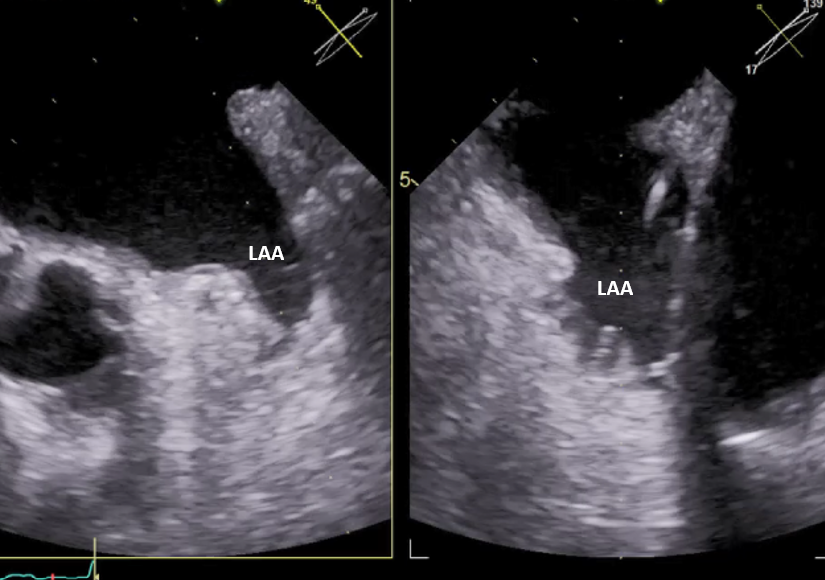

Kwalifikacja do zabiegów prowadzona jest na Oddziale Chorób Strukturalnych Serca, którego koordynatorem jest prof. Marcin Fijałkowski z I Katedry i Kliniki Kardiologii GUMed. Kluczową rolę w planowaniu zabiegów odgrywa echokardiografia przezprzełykowa i tomografia komputerowa serca. Szczegółową analizą obrazów tomografii komputerowej zajmuje się prof. Edyta Szurowska kierująca II Zakładem Radiologii GUMed oraz dr Dorota Kulawiak-Gałąska z Zakładu Radiologii naszego Uniwersytetu.

Skopia rentgenowska – okluder w uszku lewego przedsionka przed odłączeniem od systemu dostawczego